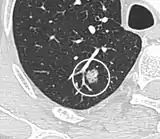

Part solid nodule.[9]

Ground glass opacity nodule.[9]